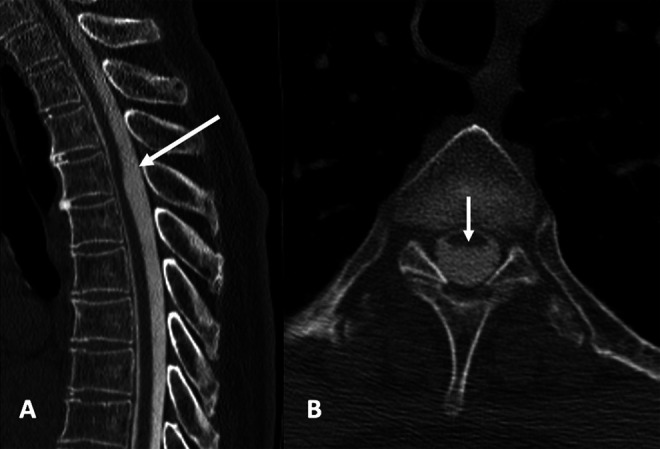

A 66-year-old woman without significant medical history other than hypertension presented with recent exacerbation of chronic back pain, progressive lower extremity weakness, gait ataxia, and mild fecal and urinary incontinence. Magnetic resonance imaging (MRI) showed ventral displacement and dorsal indentation of the thoracic spinal cord at T4–5, upstream edema at T3–4, and no evidence of syringomyelia (Fig. 1A). Cerebrospinal fluid (CSF) flow MRI (Fig. 1B) showed robust biphasic CSF flow posterior to the spinal cord at the site of compression, indicating the lack of a detectable obstructing lesion, such as an arachnoid cyst. Computed tomography (CT) myelography showed homogeneous intrathecal contrast opacification on early and delayed images (Fig. 2A), anterior cord displacement, and severe posterior cord flattening (Fig. 2B), which are suggestive of an arachnoid web.

FIG. 2.

CT myelography of the thoracic spine. A: Sagittal reconstruction clearly shows the scalpel sign (arrow). B: Axial imaging shows anterior cord displacement and severe flattening of the posterior aspect of the cord without evidence of a detectable mass (arrow).

Current radiological diagnosis of arachnoid webs relies primarily on the scalpel sign on sagittal MRI or CT myelography. The sign consists of an indentation of the posterior spinal cord that resembles a surgical scapula with the blade pointing posteriorly (Figs. 1 and 2). Direct visualization of an arachnoid web on MRI has so far been reported only once.2 Although indirect evidence of CSF flow impairment may be obtained, that did not occur with our patient (Fig. 1). Other radiological signs include spinal cord edema and syrinx formation. Most reported cases were associated with syringomyelia, usually rostral but possibly caudal to the level of indentation.5 CSF flow impediment from posterior subarachnoid space obstruction, even if not demonstrated on CSF flow studies, as in our patient, may cause a pressure gradient (Venturi effect) from intramedullary passage of CSF through perivascular spaces during systole, resulting in cord edema (Figs. 1 and 2) that eventually culminates in syrinx formation.40 Other serious diagnostic considerations are spinal cord herniation and arachnoid cyst. In spinal cord herniation, a focal anterior spinal cord protrusion through a ventral dural defect41,42 may be difficult to identify on imaging. Arachnoid cysts have well-marginated walls, cause smooth scalloping on the spinal cord surface that is seen on MRI or CT myelography,43 and behave like space-occupying lesions on CSF flow studies.